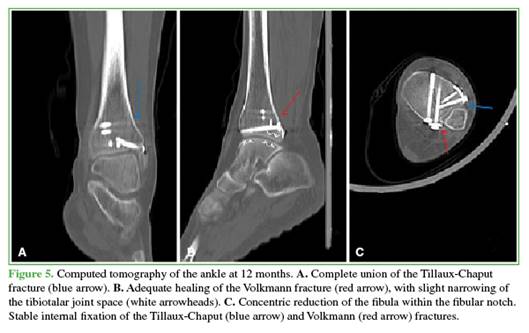

After 12 months, fracture healing was confirmed (Figures 4 and 5), and the patient resumed her usual activities. Her American Orthopedic Foot and Ankle Society (AOFAS) score was 91, and her Olerud-Molander functional scale score was 95 (Figure 6).

Thus, we present our case as a rare bimalleolar equivalent fracture: Volkmann and Tillaux in an adult, with no other associated injuries. This represents the eighth reported case in the literature over the past six decades. Reduction and fixation of both bony components were performed, successfully restoring the stability of the distal tibio-fibular ring. The patient demonstrated favorable clinical and radiological evolution, achieving functional recovery and complete fracture healing.